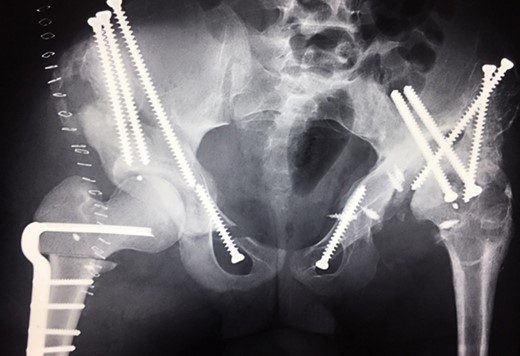

Ten years ago, a 12-year-old male presented to our clinic complaining about limping and massive swelling of the left hip. Figure 1 shows the initial X-ray and the 3D reconstruction of the left hip at first presentation when the femoral head, had already destroyed the lateral edge of the acetabulum like a mortar. Severe pain episodes have apparently not been noticed and a former hip dysplasia was not known. A brief clinical history revealed that the patient presented repeated episodes of finger biting and fevers from 2 to 8 years old. The intelligence level of the patient was at an average. The patient was admitted to a paediatric neurologist and a genetic test. A mutation of the NTRK1 gene was found and the diagnosis of CIPA was established. The right hip initially appeared to be normal and the patient was walking, therefore surgical reconstruction for the left hip was proposed due to massive swelling, inability of normal walking and significant limb length discrepancy. A Tönnis/Kalchschmidt triple pelvic osteotomy with open reduction and a shortening varus derotation osteotomy (VDRO) of the femur was performed (Fig. 2A–B). After 3 months the patient was walking again but another 3 months later the hip dislocated again without severe pain. Although the femoral head was already damaged the hip joint was reconstructed again by open reduction, capsular reconstruction with suture anchors and a trevira tube and a movable external fixator was used to temporary stabilize the joint (Fig. 3). The right hip at this time was still intact and was protected with a pneumatic orthotic device. A few months later in 2009, despite all surgeries, the left hip had entirely lost congruency and the right hip developed subluxation despite conservative treatment (Fig. 4). The patient was still walking so the decision to reconstruct the right hip with open reduction, capsular augmentation with a trevira tube, a triple pelvic osteotomy and VDRO was made (Fig. 5). Few months later this reconstruction failed as well and the hip dislocated without severe pain (Fig. 6).

(2009) Operative reconstruction of the right hip with open reduction, capsular reconstruction with trevira tube augmentation, triple osteotomy and DVO of the proximal femur to prevent destructive degeneration was performed.

(2010) Hip dislocation of the right side despite reconstruction.